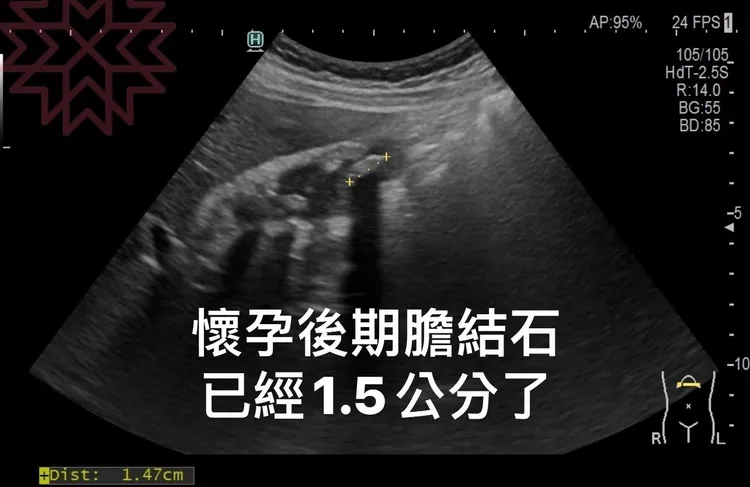

之後,做了超音波檢查,發現膽囊裡堆滿了膽結石,「而且隨著懷孕的週數 寶寶開始變大以外 連結石也一起變大,膽囊壁也開始增厚,明顯是慢性膽囊發炎,膽絞痛的症狀 」,林相宏說,能用的所有保守治療藥物都用了一輪,如胃藥PPI、膽囊放鬆劑、利膽劑、止吐藥、軟便劑、益生菌等,「全部無效,吃完飯後嘔吐可以說是家常便飯,就這樣撐到了順利生產 真的是超級辛苦」。

直到媽媽「卸貨」,症狀仍未改善 ,終於開刀把這些惱人的結石給取出,算一算總共有7顆大結石,術後終於可以慢慢恢復正常飲食,不會再嘔吐了。